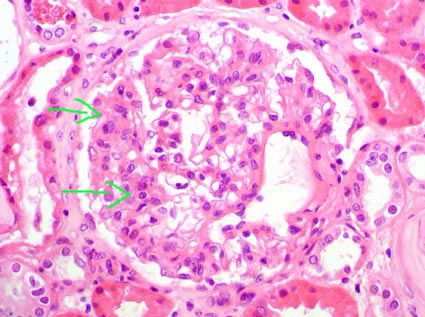

Class IV: It must have >/= 50% of glomeruli with active or chronic lesions. The lesions can be global or segmental (segmental: <50% of the glomerular tuft). If at least the half of the involved glomeruli have segmental lesions it will be IV-S, and if >/= 50% of glomeruli have global lesions it will be IV-G. If all the lesions are active (endocapillary proliferation, karyorrhexis, necrosis, hyaline thrombi, capillary wall rupture, crescents, or “wire loops”) add the designation (A); if there is at least one chronic glomerular lesion (segmental or global sclerosis) with active lesions, add the designation (A/C); and if all the glomerular lesions are chronic add the designation (C). In many globally sclerosed glomeruli is not possible to determine if the sclerosis was originated by inflammation, these glomeruli must not be classified as chronic lesions for effects to classify the biopsy in class III or IV. This class can be combined with class V, if there is subepithelial deposits (by light microscopy or IF) in 50% or more of the glomerular capillary surface area in at least 50% of the glomeruli. If I have a biopsy with 10 glomeruli and in 4 there are global active lesions and in other 2 segmental sclerosing lesions (6 of 10 with lesions) the biopsy should be classified as class IV-G (A/C), If there are 15 glomeruli and in 5 there are segmental active lesions and 4 global active lesions, this biopsy should be classified as class IV-S (A). Cases of diffuse wire loops with little or no proliferation should be included in the class IV-G (Figures 10 and 11). The IF shows, typically, diffuse subendothelial immune deposits (Figure 13)

Figure 10. In this case we can see evident subendothelial immune deposits. Left: deposits thickening capillary walls and hyaline thrombi (blue arrows) that correspond to immune aggregates in capillary lumina; they have, although often non-visible, connection with subendothelial deposits and they are not true thrombi. Right. Extensive immune subendothelial deposits, fuchsinophilic (red), in almost all the capillary walls (green arrows). These deposits, demonstrated by light microscopy, indicate class IV lupus nephritis. Many of these deposits are seen as wire loops with H&E stain. The patient of both microphotographies died due to severe SLE and microthrombi in several organs: “catastrophic” antiphospholipid syndrome. (Left: H&E, X400; right, Masson’s trichrome, X400).

Figure 11. The prominent and extensive subendothelial deposits give a rigid aspect to the capillary walls. This finding is denominated “wire loops” (arrows). These findings indicate a class IV lupus nephritis. (H&E, X400).